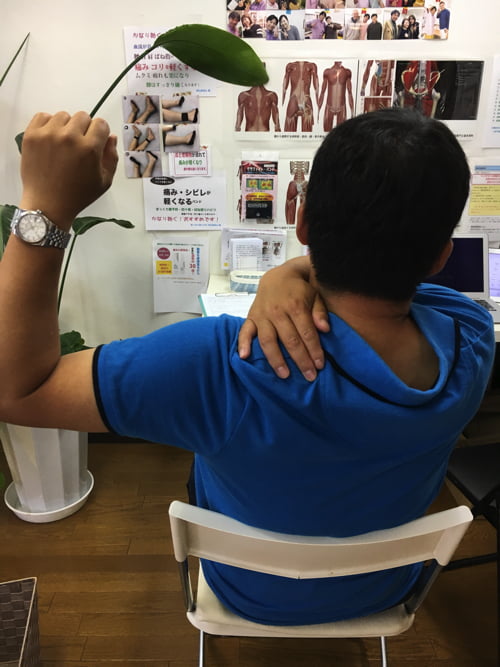

腕を上げる際に肩の痛みが出るタイプの四十肩。

腕を上げる際に、この辺りまで上げると肩付近に痛みが出てしまいます。

痛みの出る場所はこの辺りです。

この動作の際には、後ろ側に痛みが出ます。